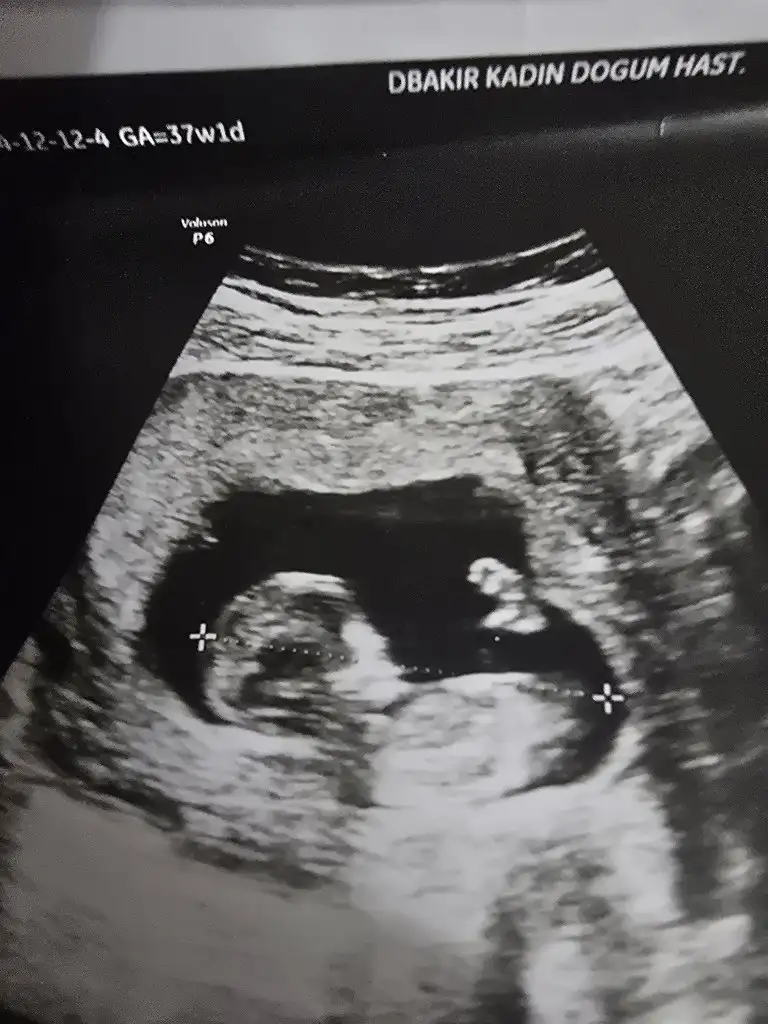

Bize de bakabilir misiniz bugün ki ultrasyondan 12+2

Bugün doktor kıza benzettim dedi, bende merakımda buraya da sormak istedimErkek olablir benimkisine benziyor![]()